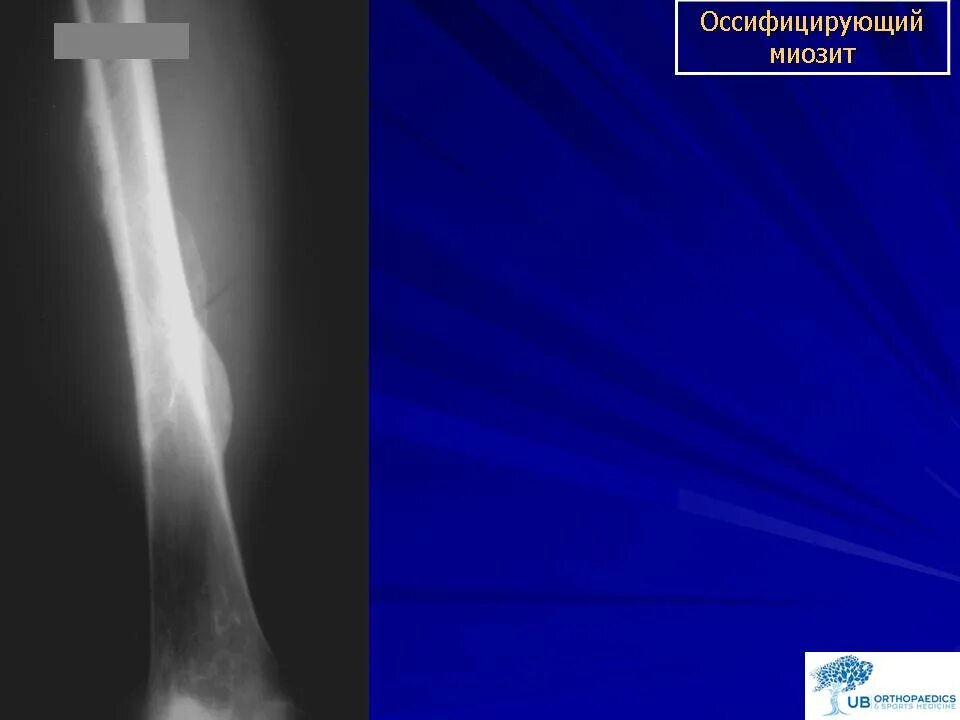

Оссифицированный миозит